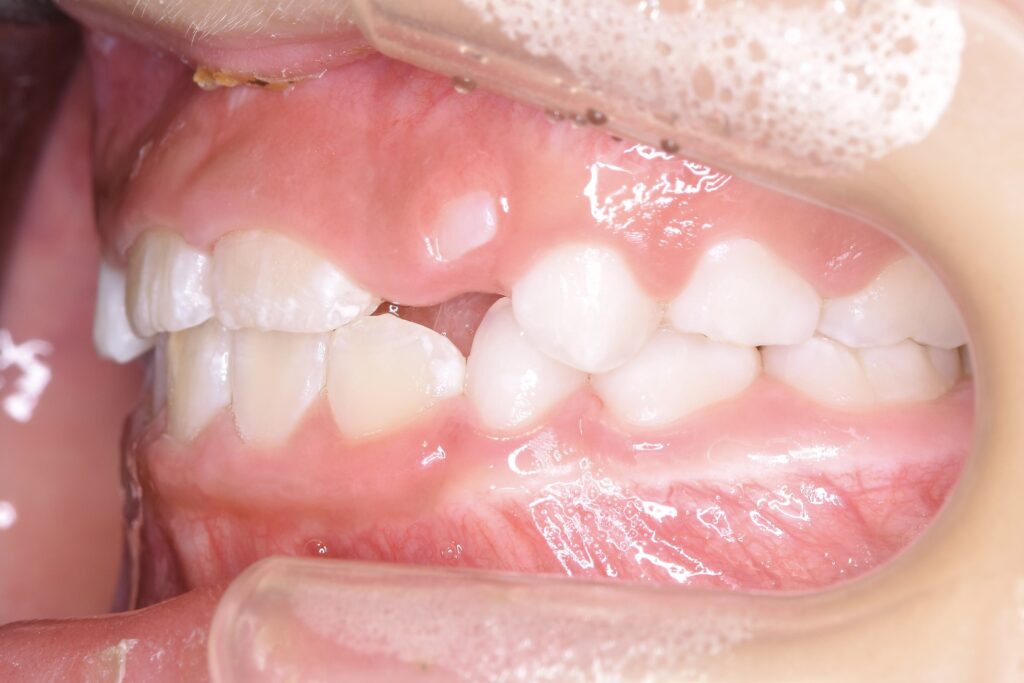

5歳 女児 小児矯正

歯並びの状態:

叢生(ガタガタ)

過蓋咬合(咬み合わせが深い)

BEFORE

主訴

右下の歯が飛び出ているので治したい。

診断名・主な症状

過蓋咬合

年齢

5歳

治療内容

上下の歯並びの幅を拡げつつ、前歯の関係を改善しました。